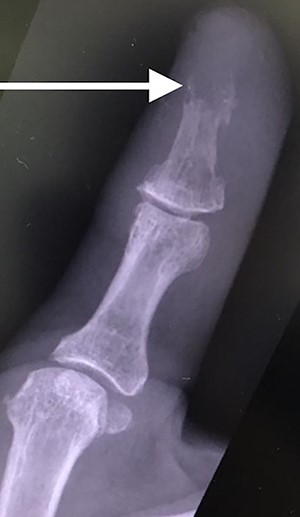

Her blood tests on presentation were unremarkable and X-rays of her right thumb showed a lytic lesion involving the tuft of the distal phalanx (Figs. 4 and 5). She was admitted to the hospital and was treated as having an infection of her right thumb with elevation and intravenous antibiotics. She underwent emergency surgery the next day for a washout and debridement of the right thumb. During the debridement in theatre, there was no pus in the pulp, but the bone was found to be eroded and soft, thus multiple specimens from the bone were sent for microscopy, culture and sensitivity, acid-fast bacilli (AFB) and histopathology.

AP radiograph of right thumb showing erosion of tip of distal phalanx.